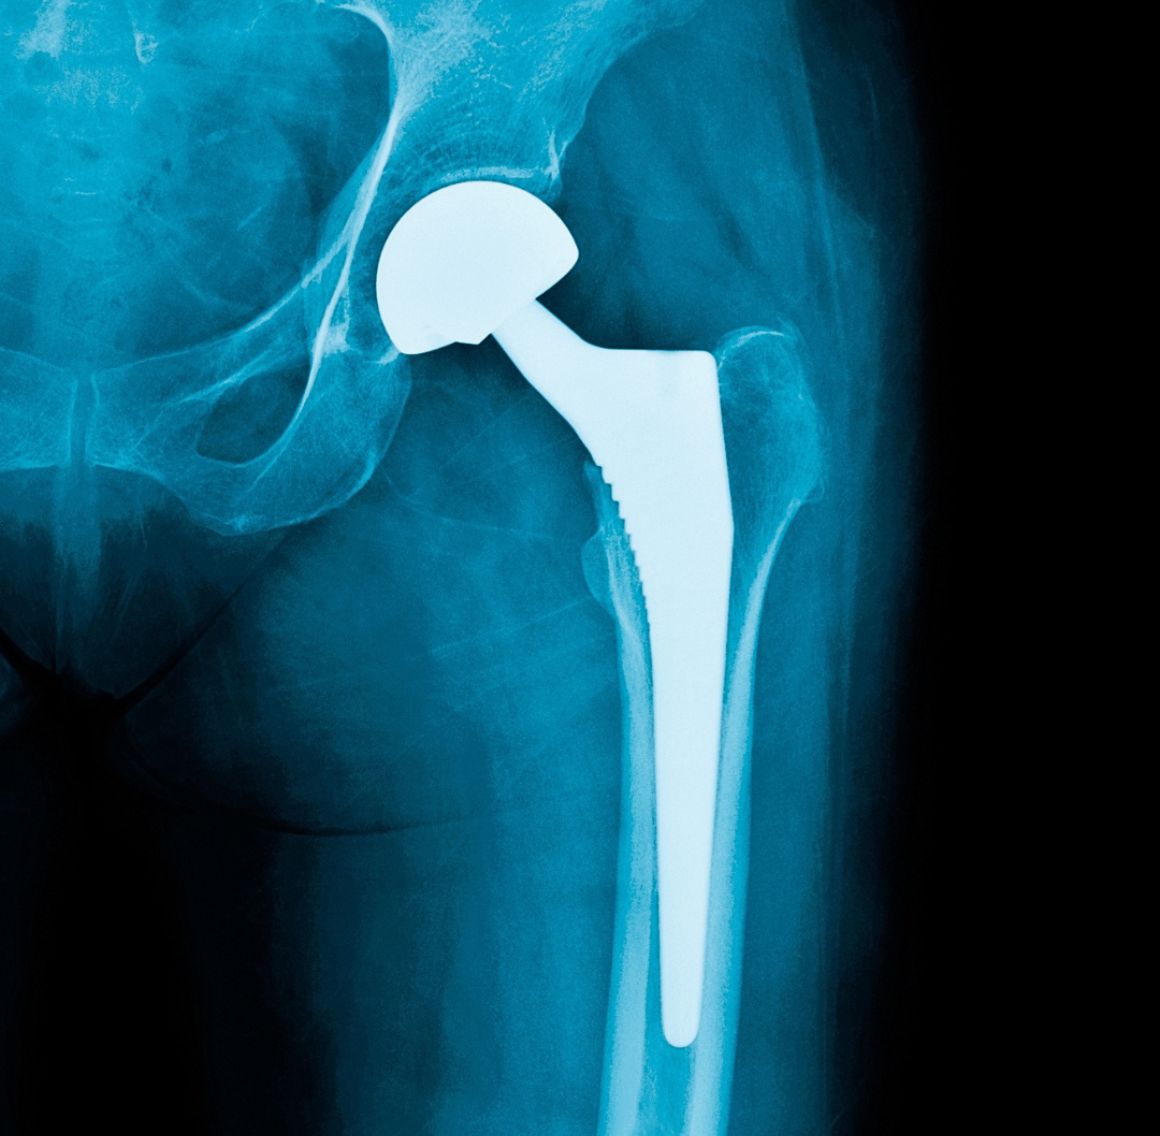

Hip Replacement Surgery involves removing the damaged or worn portions of the hip joint and replacing them with artificial components. This advanced procedure is designed to relieve chronic pain, improve mobility, and enhance overall quality of life. It is highly recommended for patients suffering from severe arthritis, hip fractures, or other debilitating hip conditions that do not respond to conservative treatments.

- Pre-Operative Evaluation: Comprehensive assessments using imaging and clinical evaluations to determine the extent of hip damage and to formulate an individualized surgical plan.

- Custom Implant Selection: Tailored prosthetic implants are chosen based on your anatomy and lifestyle needs, ensuring optimal joint function and longevity.